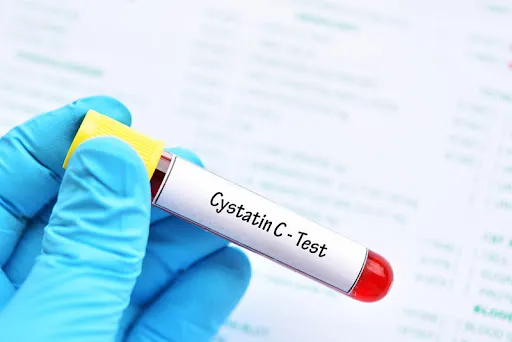

Injúria Renal Aguda (revisão Lancet 2025)

Injúria Renal Aguda (revisão Lancet 2025)